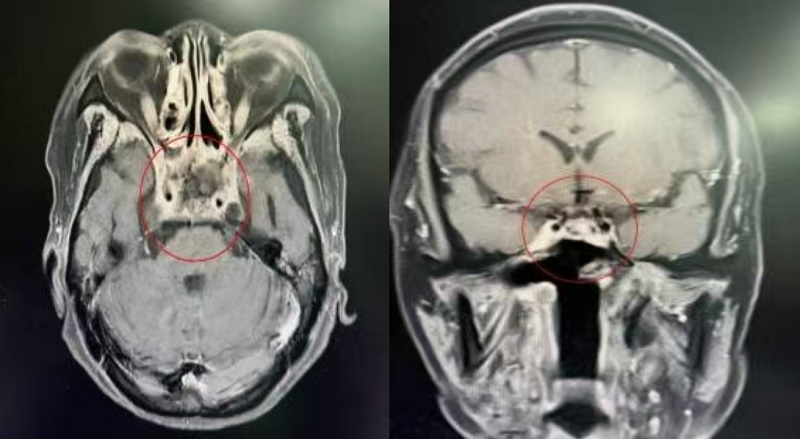

两例患者均为鼻咽癌复发经过再次放疗或化疗及靶免综合治疗后患者,病情已到极其凶险的地步:一例患者反复鼻出血,检查发现鼻咽部组织广泛坏死,颈内动脉被病变包绕,随时可能因致命性大出血而危及生命;另一例患者长期剧烈头痛,经反复抗炎治疗无法改善,辗转多家医院后发现颅底骨质及筋膜已大范围坏死,病变紧贴双侧颈动脉,破裂风险极高。

颅底结构复杂,紧邻颈内动脉、视神经等关键生命中枢,操作空间极其狭窄,稍有不慎便可能造成不可逆损伤;而放疗后组织血供差、感染风险高,传统人工材料修复又不容易存活、容易进一步加重感染等严重并发症,而能就近取材的鼻中隔黏膜瓣覆盖缺损范围小,治疗一度陷入困境。面对这一被视为“生命禁区”的手术,鼻颅底亚专科团队没有退缩。

手术中,团队以“绣花”般的精细操作,在鼻内镜的辅助下,沿着病变边界小心翼翼地清除坏死组织,在毫米级的空间内精准保护颈内动脉、视神经等关键结构,成功为患者“拆除”了潜伏在颅内的“定时炸弹”。更具突破性的是,团队摒弃了传统人工材料修复方式,采用自体带血管蒂颞肌瓣转移修复技术,通过“取己之材,补己之缺”的方式,将患者自身血运丰富的颞肌组织精准转移并覆盖在颅底巨大缺损处,重建起一道密闭、坚固的生理屏障。这一技术不仅完美解决了颅底重建难题,更凭借自体组织高存活率、强抗感染的优势,从根本上杜绝了脑脊液漏、感染致颈内动脉大出血等致命并发症,为患者的安全康复筑牢了双重防线。

得益于术前周密的规划、术中的精准操作以及术后的精心护理,两例手术均取得圆满成功。患者术后恢复远超预期,住院期间未出现脑脊液鼻漏、颈内动脉大出血及严重感染等并发症,头痛、鼻出血等症状也迅速缓解,颞肌瓣存活良好,患者顺利康复出院。